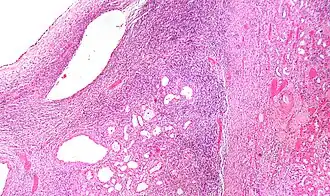

| Micrografia de um nefroma cístico (centro) com rim saudável a direita. | |

Histologicamente os cistos são envolvidos por um epitélio simples com núcleos em direção ao núcleo do cisto ("epitelio em prego"), estroma tipo ovariano, células fusiformes e citoplasma basofílico. No estroma possui receptores para estrógeno e progesterona.[4]